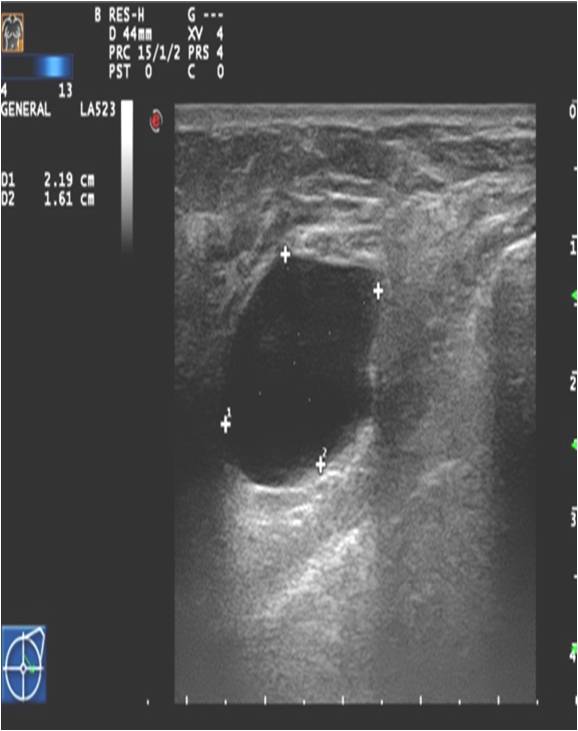

Ultrasonography can help in their differentiation; can depict anechoic cystic lesions (Picture17.) or solid masses (Picture 18.). These lesions usually each have a smooth, sharp edge and echo-enhancement can appear behind them. Rarely, cysts contain tumors. (Picture19.).

Image

Picture 17.

Picture 18

Picture 19

Picture 20.